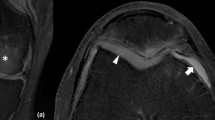

Fat-suppressed T1-weighted gradient-echo images depict subchondral bone as dark, cartilage as hyperintense, and synovial fluid as lower in signal intensity (Fig. 1). Because a 3-D dataset can be obtained, they are considered ideal for quantitative assessment of cartilage thickness and volume [9]. One drawback is that they are time-consuming (6–15 min) especially when high-resolution images (0.3–0.4 mm in-plane, 1–2 mm slice thickness) are obtained. In addition, gradient-echo images are not ideal for the evaluation of other joint tissues, such as ligaments and menisci.

Fast-spin echo images (Fig. 2) are typically performed with proton density weighting and depict cartilage as intermediate in signal intensity, fluid as hyperintense, and subchondral bone as hyper- or hypointense depending on whether fat-suppression is used. Because fast-spin echo images are 2-D, they are not used for quantitation of cartilage thickness and volume, but they can be used to assess other joint structures, such as ligaments and menisci.